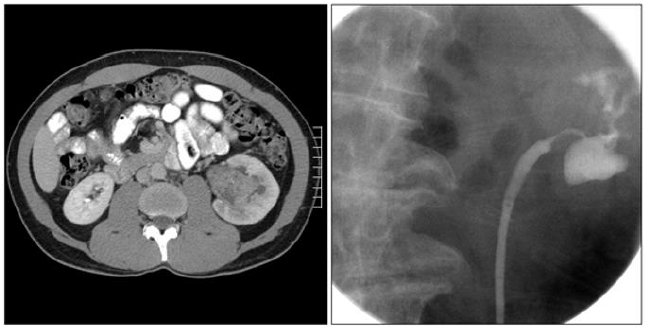

Homem, 70 anos, branco, tabagista, com história prévia de ressecção transuretral de tumor de bexiga por duas vezes. Consulta por novo episódio de hematúria macroscópica com coágulos, dessa vez associada à dor abdominal. Citologia urinária positiva para células neoplásicas. Realizada cistoscopia sem identificação de lesões ou massas suspeitas. Observe o estudo de imagens:

Considerando o caso clínico, qual diagnóstico mais provável?